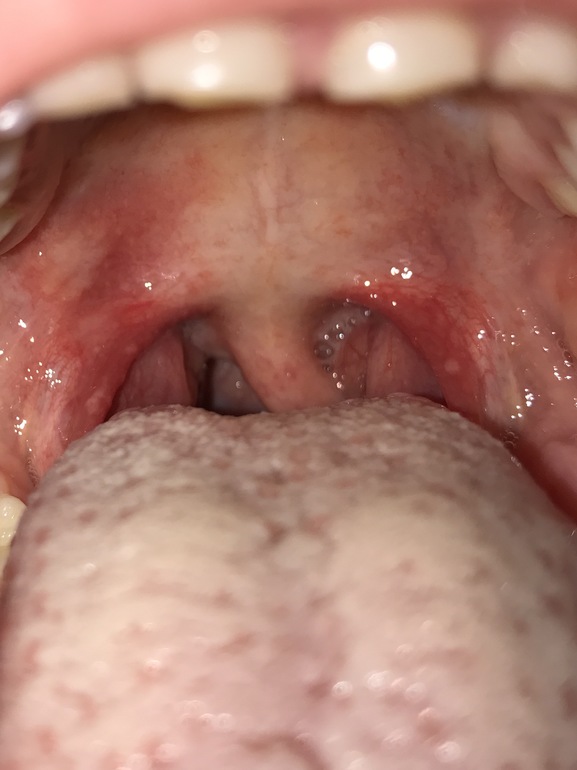

ЛОР (отит, насморк и проч)Девочки,замучались мы уже с этим нашим горлом;(может у кого то такая же картина была и как то нашли способ победить бяку.Постоянно болит горло,миндалины воспаляются,какие то сиранные белые точки редкие.Лечили и физио процедурами,аетибиотиками,Тонзилгоном,полоскаем хлорфиллиптом,прополисом,всякими возмоджными полоскалками,пропили Флемоксин по назначениб врача,Амиксин пили курсами,кагоцел,иммудон...толку ноль..фото под катом.

в том то и дело, что когда полоскалки - образ жизни, то слизистая просто не может вернуться в нормальное состояние. уберите все механическое воздействие на горло. вместо полосканий используйте смазывание миндалин не люголем (хотя я его тоже использую, но не в начале болезни, а в период выздоровления, иначе он может сжечь слизистую), а мазями с антисептиками например гиоксизон. "Точки" на дужках пусть будут, если нет болевых ощущений не стоит их лечить. На фото нет сильного налета, т.е. это не запущенная бак инфекция, скорее хроническое красное горло.